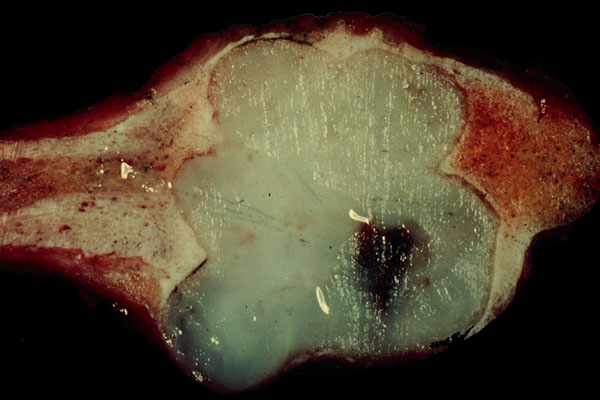

Chondrosarcoma, gross

Characteristic gross appearance of

chondrosarcoma

, i.e. a translucent firm, bluish

gray

lesion, with smooth, shiny cut surfaces.